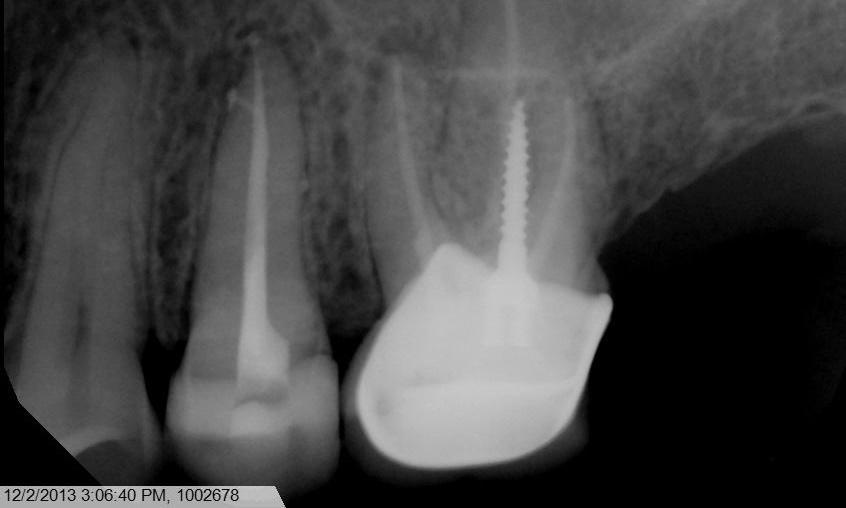

Root canal treatment. With the system we use, warm vertical fill of gutta percha is able to fill in lateral, or accessory, canal, which is difficult to achieve with traditional root canal treatment method.